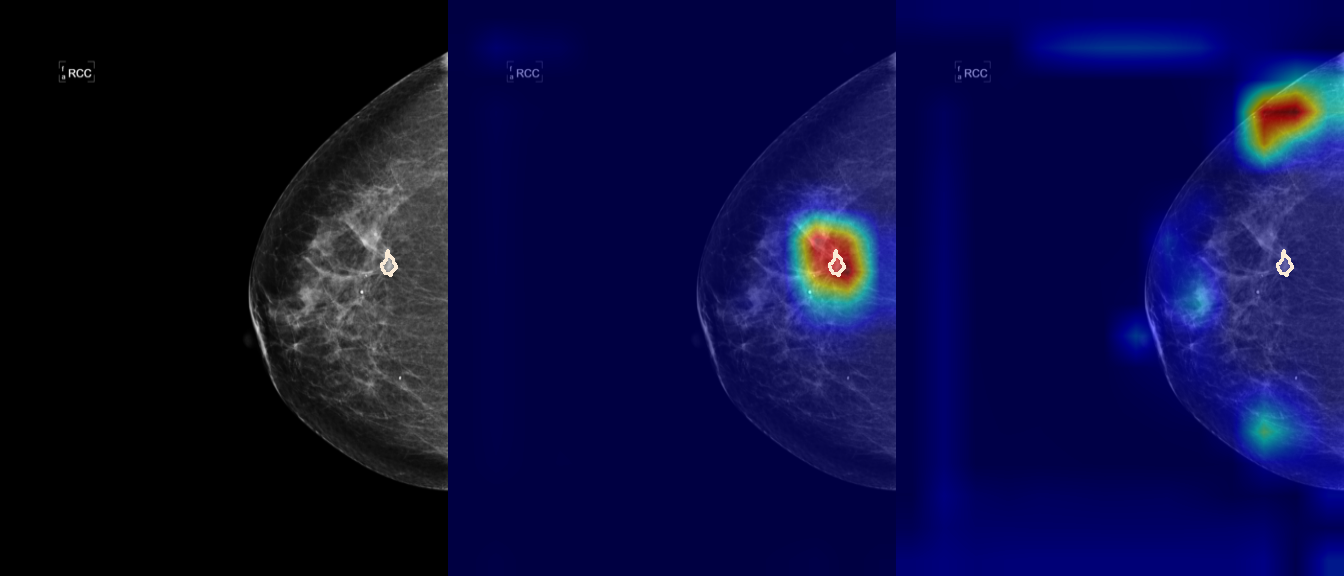

To interpret the decision-making process behind the quantitative results, we visualized Class Activation Maps (CAM) for the top-performing methods, ERM and VREx. Figures 1 through 2 illustrate discriminative regions identified by the models within the full mammograms.

Localization of Clinical Features: A key concern in medical AI is whether high performance stems from genuine pathology detection or spurious background correlations. Our visualizations suggest that Standard ERM achieves its superior quantitative performance by predominantly prioritizing clinical cues. As shown in the top rows of the Figure 1 and Figure 2, the ERM-trained models consistently focus attention on the specific lesion regions within the breast tissue. This demonstrates that despite lacking explicit invariance constraints, ERM is capable of learning robust, medically relevant features when trained on diverse multi-source data.

Attention Drift in Both Methods: While both ERM and VREx generally identify the correct region of interest in successful cases, neither method is immune to attention drift. We observe instances in both training paradigms where the model focuses on irrelevant areas, such as healthy fibroglandular tissue or background artifacts (e.g., rows 5 and 6 in Figure 1). This indicates that while VREx is designed to penalize instability, it does not guarantee perfect anatomical focus compared to the unconstrained ERM baseline.